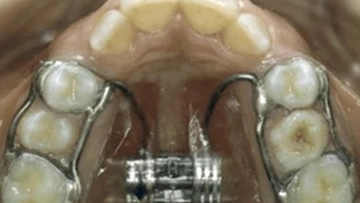

Dogo Çenesinin Gücü Ne Kadar Ton Basabiliyor?Dogo Argentino, güçlü yapısıyla dikkat çeken bir köpek ırkıdır. Bu ırk, av köpeği olarak yetiştirilmiş olup, kaslı yapısı ve güçlü çenesi ile bilinir. Dogo Argentino'nun çene gücü, hem avcılık yetenekleri hem de koruma işlevleri açısından oldukça önemlidir. Bu makalede, Dogo'nun çene gücünü detaylı bir şekilde inceleyeceğiz. Dogo Argentino'nun Çene AnatomisiDogo Argentino, güçlü bir çene yapısına sahip olmasıyla birlikte, bu güçlü yapı birkaç anatomik özellikten kaynaklanmaktadır:

Çene Gücü ve Basınç ÖlçümüBir köpeğin çene gücünü ölçmek için genellikle "bite force" (ısırma gücü) terimi kullanılır. Dogo Argentino'nun çene gücü, 450 psi (pound per square inch) civarında ölçülmüştür. Bu, Dogo'nun çenesinin yaklaşık 20-30 ton basma kapasitesine sahip olduğu anlamına gelir. Bu güç, Dogo'nun avını yakalama ve tutma yeteneğini büyük ölçüde artırır. Çene Gücünün ÖnemiDogo Argentino'nun çene gücü, birkaç açıdan önem taşımaktadır: